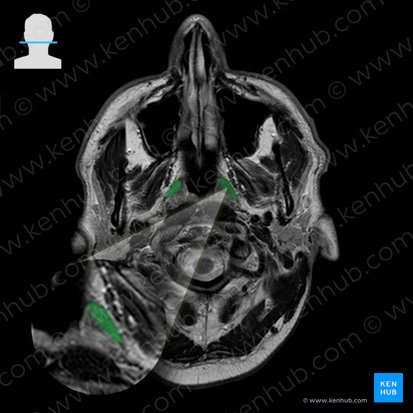

Levator veli palatini is a paired cylindrical muscle situated lateral to the choanae of nasal cavity, spanning from the petrous part of temporal bone to the superior part of palatine aponeurosis. Together with tensor veli palatini, palatoglossus, palatopharyngeus muscles and musculus uvulae, levator veli palatini comprises the soft palate

Levator veli palatini is divided into superior and inferior parts based on its origin points. The superior part originates from the inferior surface of the petrous part of temporal bone, anteriorly to the inferior opening of carotid canal and posteriorly to the origin of tensor tympani muscle. The inferior part of the muscle originates from the inferior part of medial lamina of cartilage of auditory (Eustachian) tube and from the vaginal process of sphenoid bone.

From these origin sites, the muscle fibers course inferomedially towards the soft palate. After passing through a narrow space between the two layers of palatopharyngeus muscle, levator veli palatini muscle inserts onto the superior aspect of palatine aponeurosis where it interlaces with the fibers of its contralateral counterpart.

The superior part of the muscle lies posteromedial to tensor veli palatini muscle and lateral to tubal tonsils and cartilaginous part of auditory tube. The distal part of the muscle separates the palatopharyngeus muscle into two layers, through which it reaches its insertion.